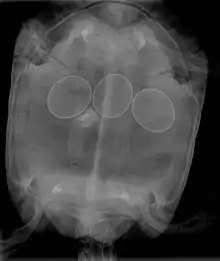

In reptiles, it is inadvisable to attempt to break a reptile egg to remove it from an egg-bound female. This procedure may be done by a veterinarian, who will insert a needle into the egg, and withdraw the contents with a syringe, allowing the egg to collapse and be removed. Non-surgical interventions include administering oxytocin to improve contractions and allow the egg(s) to pass normally. In many cases, egg-bound reptiles must undergo surgery to have stuck eggs removed.